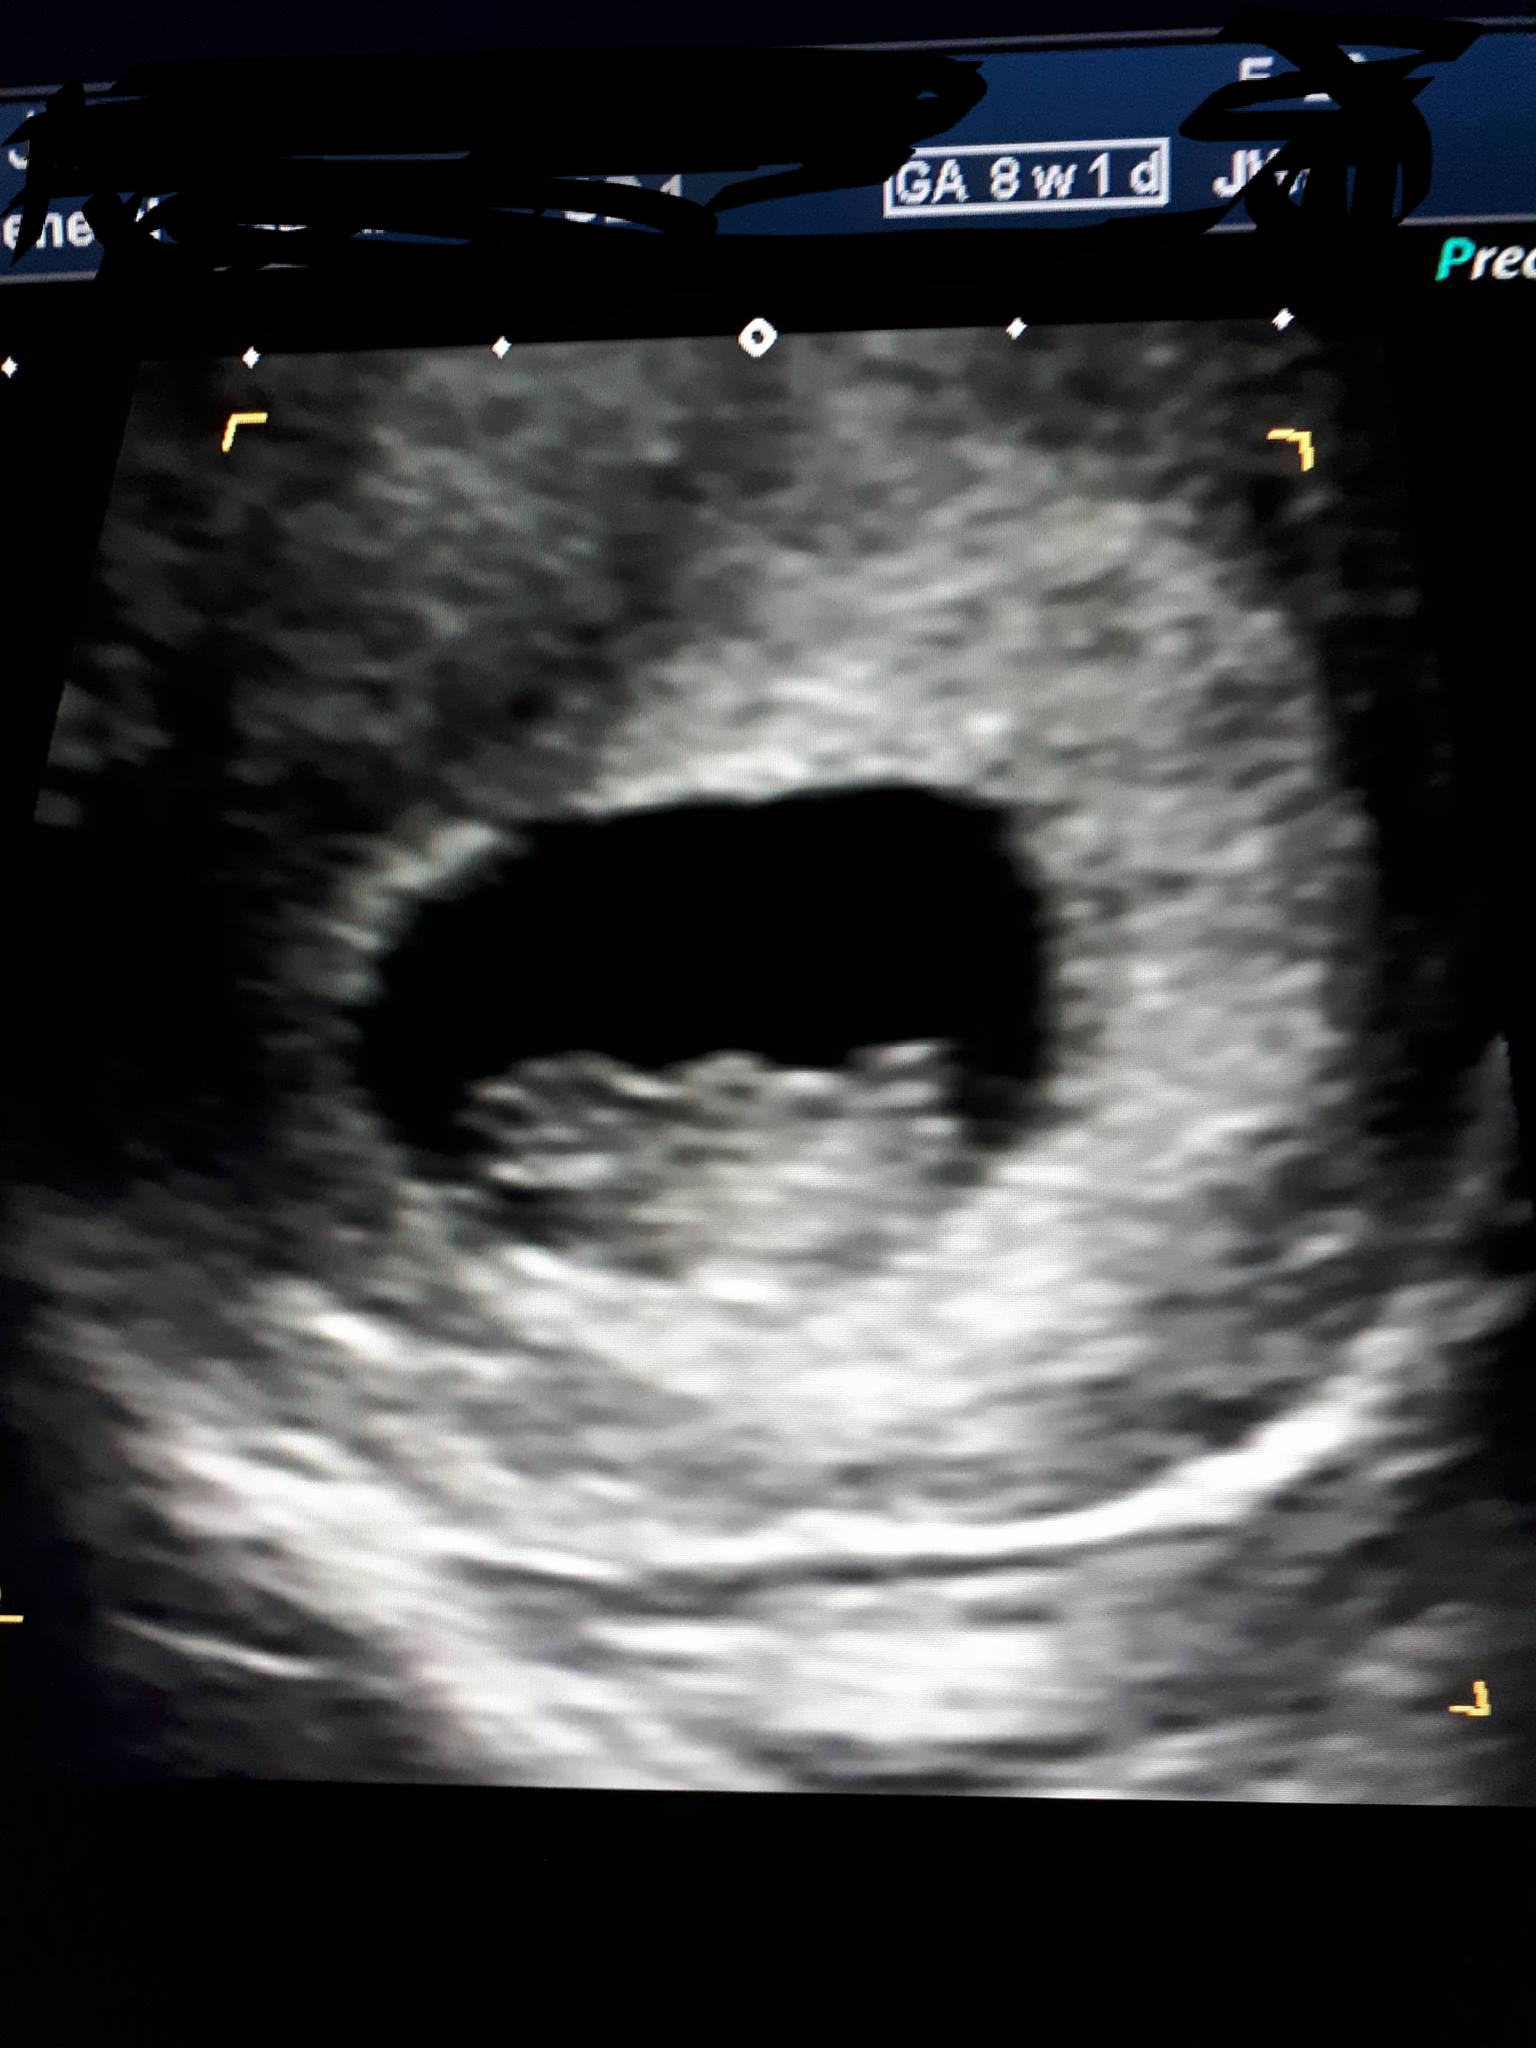

Attachment 38160Attachment 38161Attachment 38162

Ramzi has been debunked and 11 weeks is too early for a nub guess, sorry. If you happen to get a nub shot between 12-13 weeks, I'd be happy to guess!